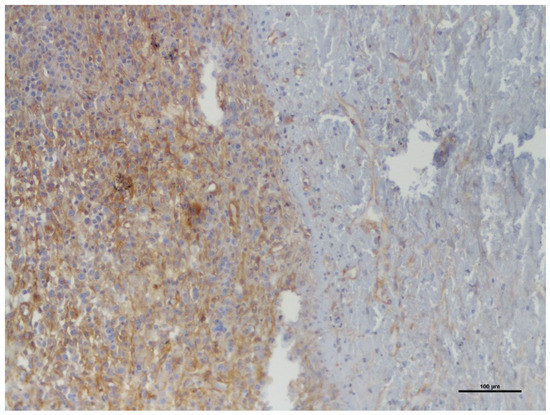

Background and Clinical Significance: Neurofibromatosis type 1 (NF1) predisposes individuals to various peripheral nerve sheath tumors (PNSTs), including benign neurofibromas, malignant peripheral nerve sheath tumors (MPNSTs), and intermediate lesions known as atypical neurofibromatous neoplasms of uncertain biologic potential (ANNUBP), previously often termed atypical neurofibroma. These atypical lesions are considered premalignant precursors to MPNST. Case Presentation: We present the case of a 33-year-old male with NF1 who developed a rapidly growing, painful mass in his right calf. Clinical examination revealed signs consistent with NF1. Magnetic resonance imaging showed a large, heterogeneous mass in the lateral compartment. Biopsy revealed a neurofibroma with hypercellularity, moderate atypia, scarce S100 positivity, focal CD34 positivity, and an elevated Ki-67 proliferation index of 10–12%, consistent with ANNUBP. The patient underwent wide surgical resection, including the fibula and peroneal muscles. At the 30-month follow-up, there was no local recurrence, though the patient had a mild residual limp. Discussion: This case highlights the clinical presentation, diagnostic features, and management considerations for ANNUBP in NF1, emphasizing the importance of recognizing warning signs and the role of pathology in guiding treatment for these high-risk precursor lesions. Full article

Figure 1